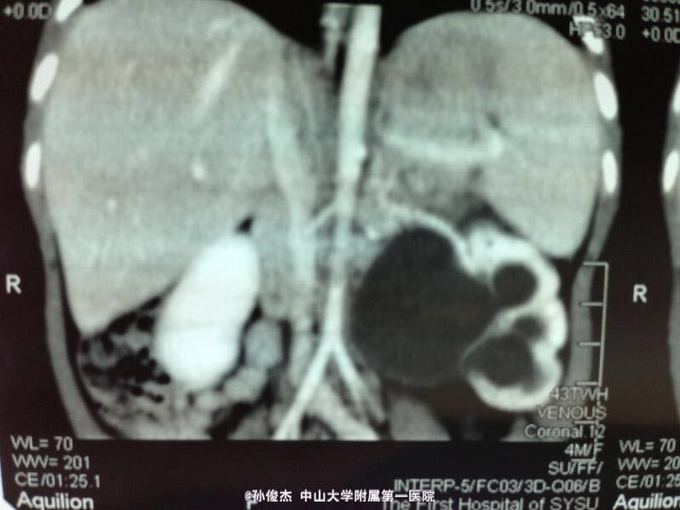

女孩,四个月。产前检查发现左肾积水,出生后超声随访逐渐加重,四月龄时至我院。

超声检查左肾积水5.9*4.3cm,ECT:左肾GFR26.8ml/min明显降低,右肾GFR59.8ml/min正常范围。CT示左肾积水,左肾盂输尿管连接处梗阻。